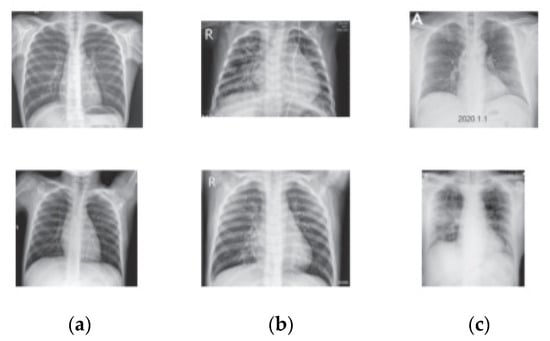

On the other hand, COVID-19 public dataset in [] is also used to validate the proposed method. This dataset consists of 460 COVID-19, 1266 normal, and 3418 pneumonia training X-ray images and 116 COVID-19, 314 normal, and 855 pneumonias for testing. The main critical issue in this dataset is that it contains pneumonia that is caused by bacterial infection and not COVID-19. Figure 9 illustrates images that are randomly selected from the class samples.

Figure 9. COVID-19 X-ray Samples: (a) Normal, (b) Pneumonia, (c) COVID-19.